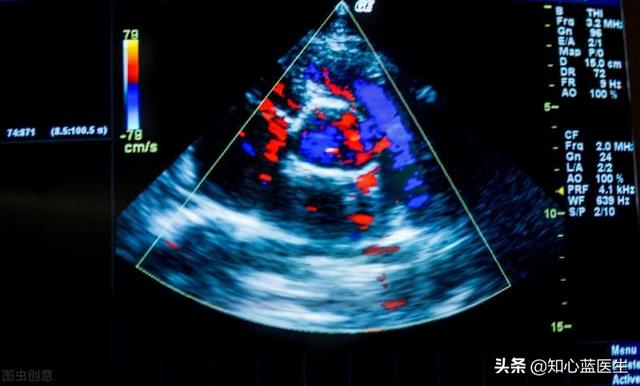

L'échographie cardiaque est une sorte de règle qui permet d'évaluer la taille du cœur, sa mobilité, sa contractilité et sa résistance.

- L'échographie cardiaque est basée sur le principe des ondes sonores.Il reçoit les ondes sonores réfléchies par le cœur et les convertit en images sur l'appareil d'échographie cardiaque, ce qui permet de mesurer directement la taille des oreillettes et des ventricules du cœur, la contractilité du cœur, l'état des valves et l'activité du cœur.Cependant, l'échographie cardiaque ne permet généralement pas de voir directement s'il y a un rétrécissement ou une obstruction des artères coronaires.

- Les formes plus légères d'ischémie myocardique et de coronaropathie ne présentent généralement pas de modifications de la taille du cœur, de la contractilité cardiaque ou de l'activité cardiaque.Ainsi, si l'échographie cardiaque semble normale ou essentiellement normale, elle ne prouve pas l'absence d'ischémie myocardique ou de maladie coronarienne.

- L'ischémie myocardique sévère, la maladie coronarienne ou même un infarctus du myocarde relativement important peuvent être clairement visibles à l'échographie cardiaque sous la forme d'une modification de la contractilité cardiaque.Les symptômes de l'ischémie sont des changements dans l'activité du myocarde et même des anomalies dans le fonctionnement des valves cardiaques. On peut ainsi déduire indirectement que le myocarde souffre d'une ischémie sévère.

5, échographie cardiaque : l'échographie cardiaque permet d'observer le muscle cardiaque et l'anatomie interne de l'examen ; elle ne peut pas voir directement les artères coronaires, mais en cas d'ischémie ou de nécrose du myocarde, elle affectera le mouvement du myocarde, de manière à répondre indirectement à la situation de l'approvisionnement en sang du cœur ;

7. échocardiographieIl s'agit d'un test non invasif qui examine la structure et la fonction du cœur. L'ischémie ou l'infarctus est déterminé en examinant le mouvement, l'épaisseur, etc. de la paroi ventriculaire. En cas d'ischémie, le mouvement de la paroi ventriculaire est affaibli et non coordonné, et le myocarde infarci est aminci, voire ne bouge pas (se contracte) ou bouge dans la direction opposée (se contracte), ce qui est médicalement connu sous le nom de "tumeur de la paroi ventriculaire", et il peut également y avoir un "thrombus de la paroi attachée". Chez les patients présentant des infarctus importants, la fonction cardiaque mesurée par échographie peut être réduite.

5. échographie cardiaque

L'échographie cardiaque permet de déterminer s'il y a rupture ou épaississement des parois auriculaires et ventriculaires, si les oreillettes et les ventricules sont élargis, s'il y a sténose ou fermeture insuffisante des valves cardiaques, si les fonctions systolique et diastolique du cœur sont normales et si la fraction d'éjection est normale.